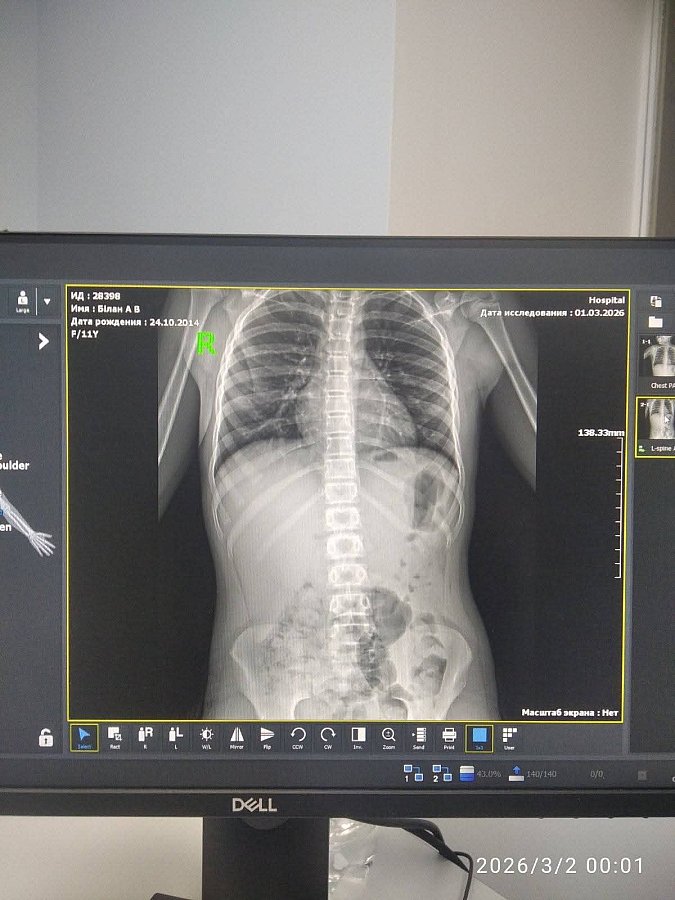

Согласно медицинской выписке, у девочки диагностировали сотрясение головного мозга, ушиб органов брюшной полости и ушибы конечностей. Мать утверждает, что после происшествия не получила никакой поддержки от администрации школы.